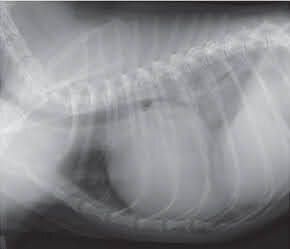

犬の心臓のレントゲン画像

参考・写真/「いぬのきもち」2018年7月号『3号連続企画 犬の死因トップ3を学ぼう!知っておきたい犬の「心臓病」』

• 逆流はまだないが、将来僧帽弁閉鎖不全症になるリスクが高い犬種。

• 治療の必要はないが、該当する犬種や年齢の犬は定期的な検査をする。

ステージB1

• 軽度の逆流が認められる状態。通常、症状は認められない。

• 日常生活のアドバイスを行い、3~6か月の間隔で定期検査をする。

ステージB2~治療開始の目安